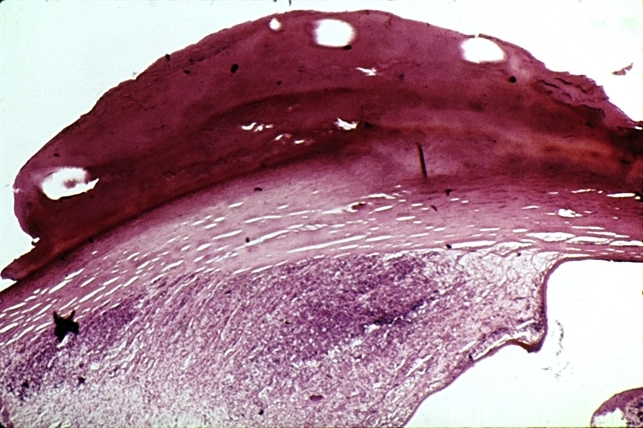

- plaque, cornea

- Epinephrine plaque of the cornea.